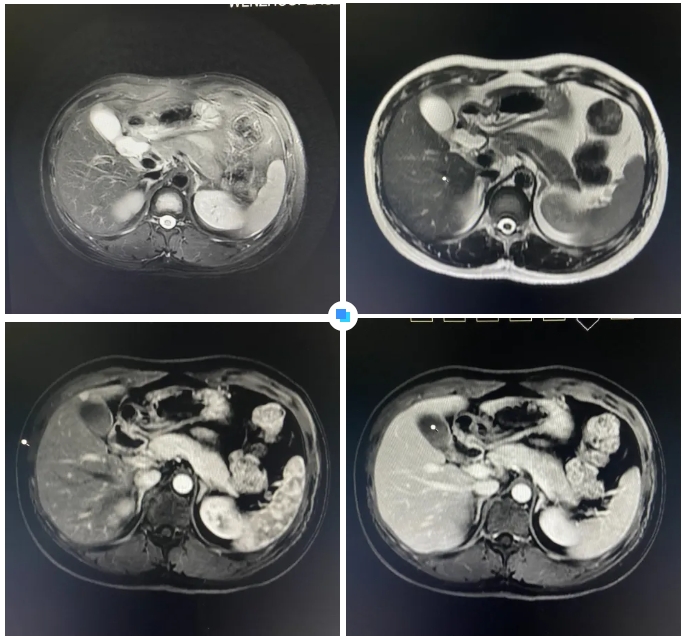

在被問到如何發現隱藏如此深的病灶時,和平國際醫院影像中心執行主任侯文杰講到,該病灶在平掃T1、T2項都非常不清楚,只有彌散加權的情況下,病灶區域顯示出輕微的高信號,這一細微線索引起了他的高度關注。

隨后的增強核磁掃描發現,在動脈期病灶顯著強化,而在門脈期明顯減退,這一特征與微小肝癌的表現高度吻合。